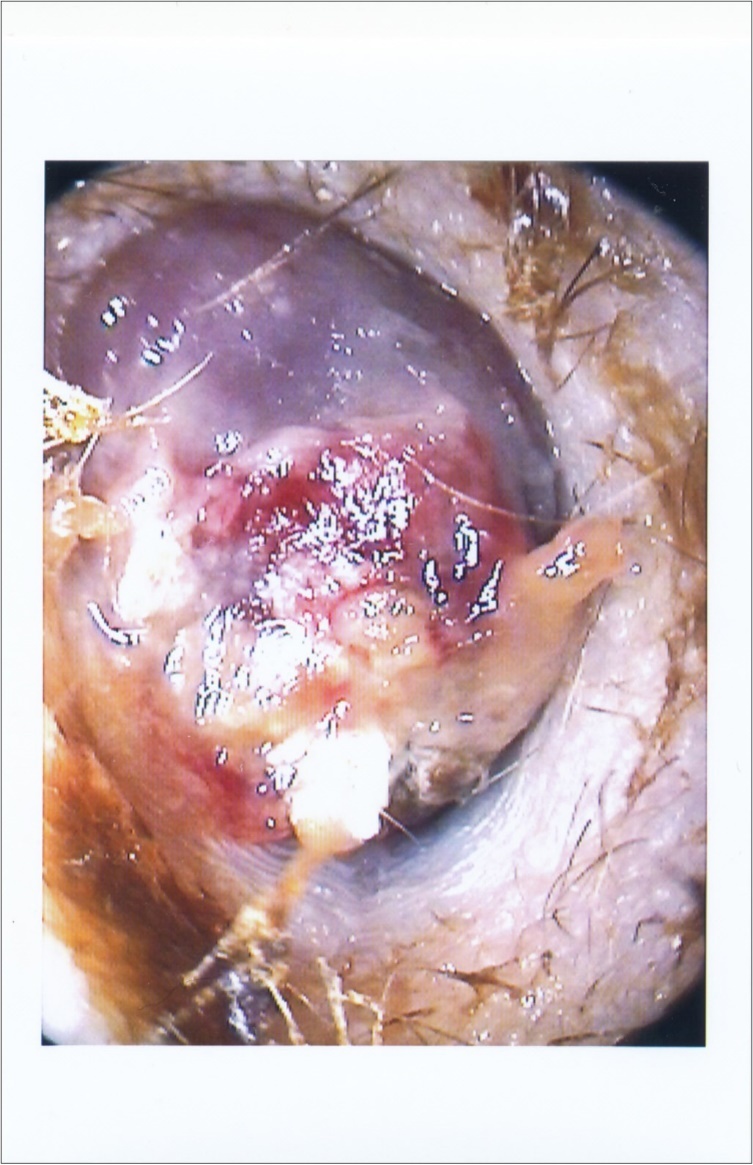

when the facial nerve paralysis started, it was House-Brackmann grade V/VI. The external canal was fully occluded with reddish-purple soft mass with bleeding on touch. (Figure 1). There was no redness or narrowing in external canal skin. No lymph nodes detected. Her nasal and throat examination was clear. The rest of neurological examination was normal. She didn’t have any weight loss nor night symptoms of increase temperature or sweat. The audiogram showed conductive hearing loss with air-bone gap 20 dB at 1000 Hz.

Figure 1.Right ear shows reddish-purple mass

The current report has the typical presentation of early deafness and facial paralysis. The lymphoma has a rapid progressive course in the ear than any other skin malignancy. The presentation is different from any inflammatory condition. It lacks the typical deep nocturnal otalgia of NOE in addition to the resistance to medical treatment. The soft tissue mass of external canal is grossly different from the granulation in NOE or the polyp of middle ear cholesteatoma. It is deep purple large mass and bleeds easily on touch. Finally, skin of external canal won’t show signs of acute inflammation. It isn’t hard to say that superimposed infection will make clinical diagnosis difficult. It is always recommended to biopsy any persistent polyp after treatment or any mass in external auditory canal especially in immune compromised patients.